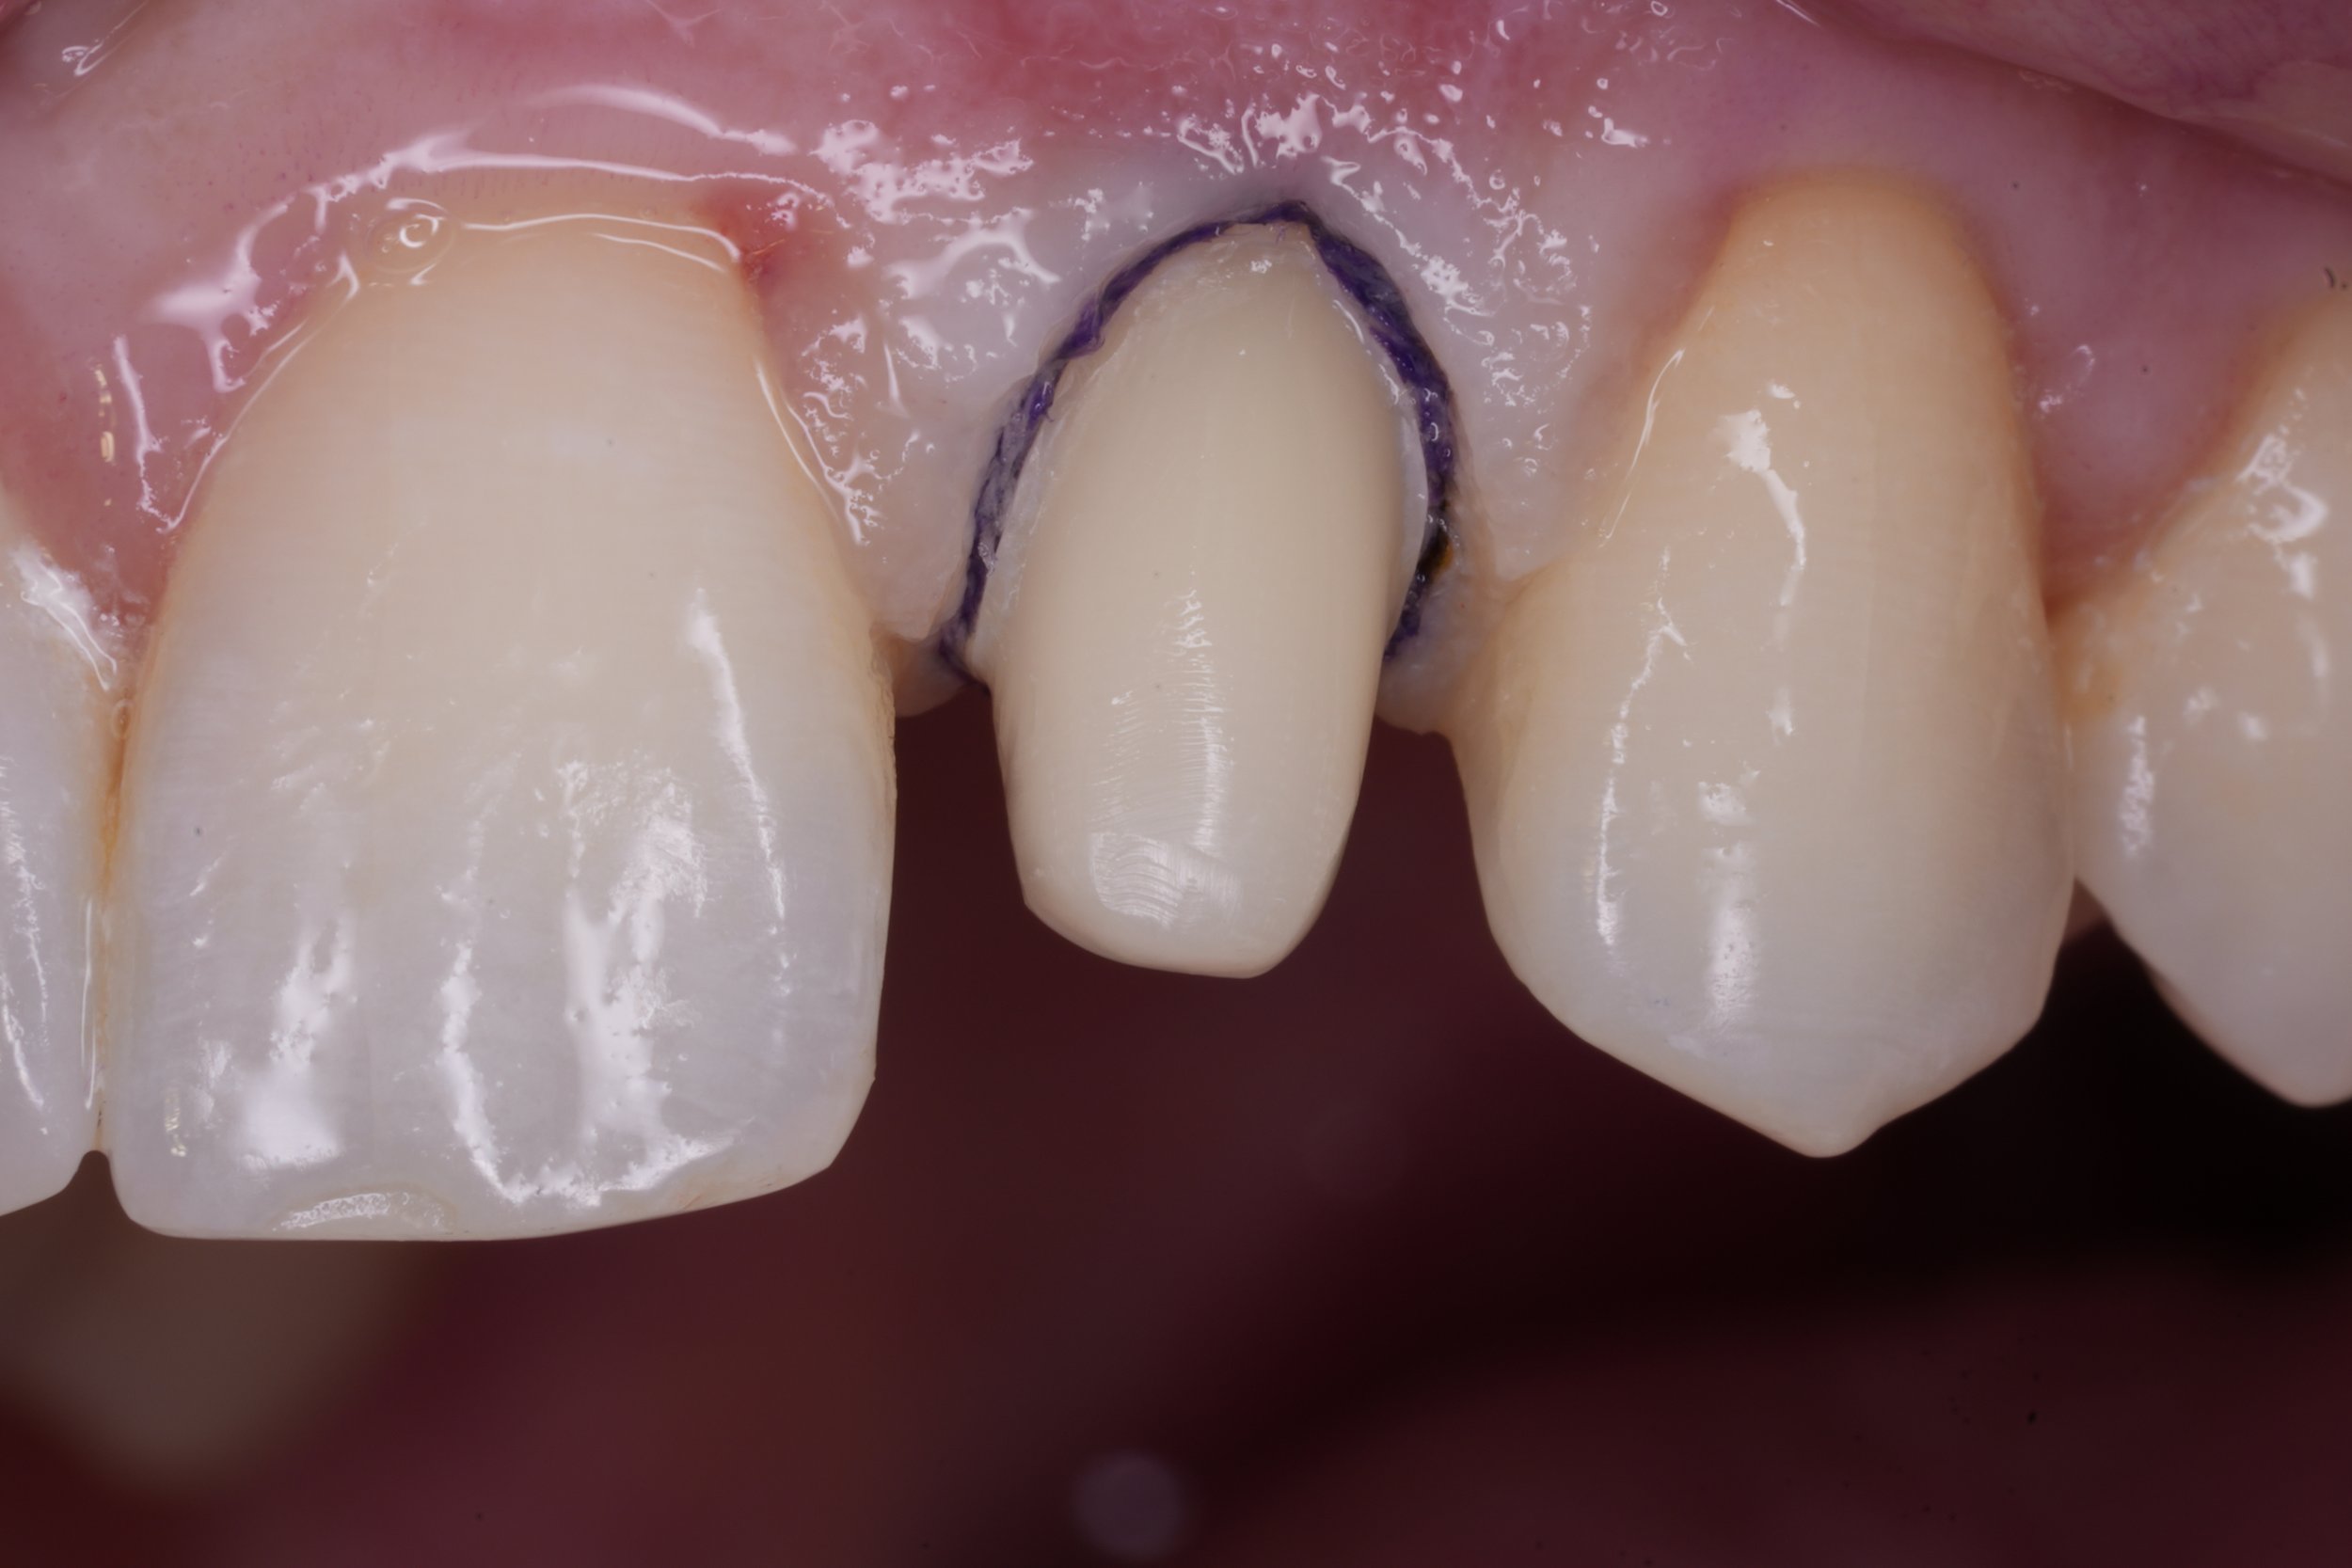

Fixed pros